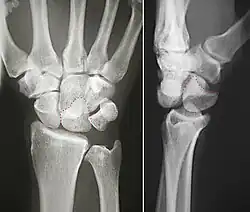

The lunate bone (semilunar bone) is a carpal bone in the human hand. It is distinguished by its deep concavity and crescentic outline. It is situated in the center of the proximal row carpal bones, which lie between the ulna and radius and the hand. The lunate carpal bone is situated between the lateral scaphoid bone and medial triquetral bone.

Structure

The lunate is a crescent-shaped carpal bone found within the hand. The lunate is found within the proximal row of carpal bones. Proximally, it abuts the radius. Laterally, it articulates with the scaphoid bone, medially with the triquetral bone, and distally with the capitate bone. The lunate also articulates on its distal and medial surface with the hamate bone.[2]: 708 [3]

The proximal surface of the lunate bone is smooth and convex, articulating with the radius. The lateral surface is flat and narrow, with a crescentic facet for articulation with the scaphoid bone. The medial surface possesses a smooth and quadrilateral facet for articulation with the triquetral bone. The palmar surface is rough, as is the dorsal surface. The dorsal surface is broad and rounded. The distal surface of the bone is deep and concave.[4]

The lunate bone is the most frequently dislocated carpal bone.